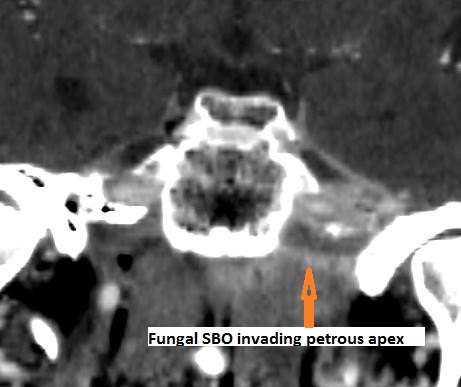

Skull base osteomyelitis (SBO) not related to necrotizing otitis externa (NOE) as described above.

Petrous apicitis with an etiology other than associated with middle ear and mastoid disease.